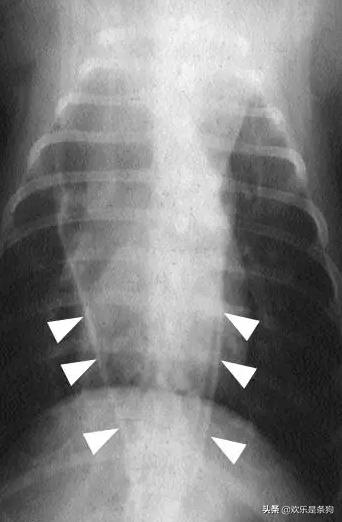

狗狗食管扩张X光片

消化道的X线钡餐造影是确诊犬巨食症的关键,X光显示犬食道又大又黑,再结合呕吐物性状及PH值,方可确诊。